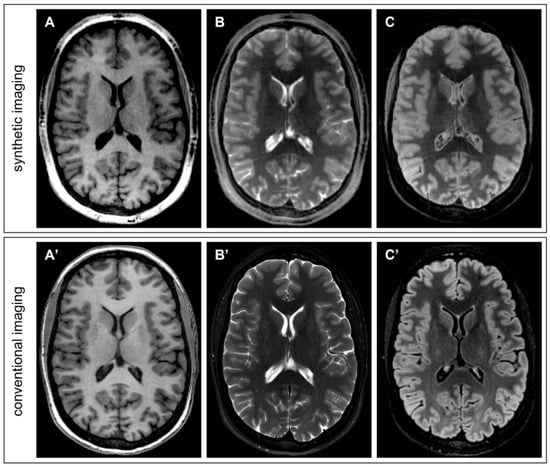

- Synthetic T1-weighted images simulating GRE (Gradient-recalled Echo) were synthesized with the following equation, incorporating the input maps of PD and T1 and setting the simulated acquisition parameter TR:

- Bias-free T1-weighted MPRAGE was synthesized by taking into consideration that B1 bias in QTI is incorporated in the PD map, which can be excluded from the formula, achieving a similar appearance to MP2RAGE uniform imaging [15]:

- Synthetic T2-weighted images simulating a SE (Spin Echo) acquisition were obtained as follows:

- Synthetic T2-FLAIR was obtained with a user-modified formula incorporating a coefficient TSAT, which enables the introduction of T1-weighting, which better mimics the one in conventional imaging: